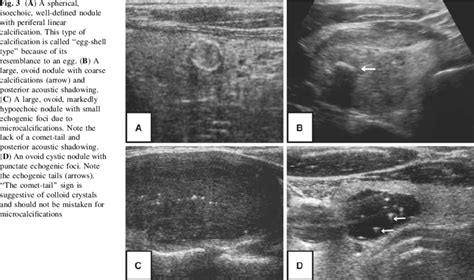

Isoechoic nodule meaning. 1D —Categories of echogenic foci. Entire nodule has il...